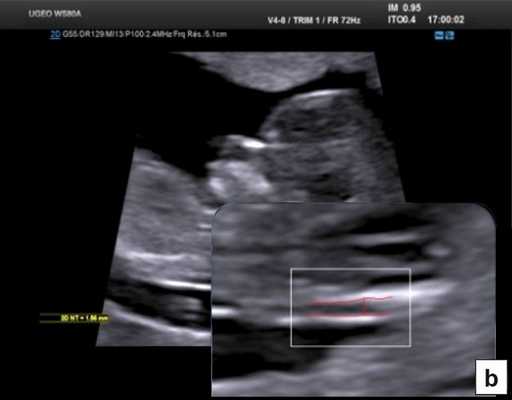

В начале 90-х годов прошлого века в практику был внедрен метод измерения толщины воротникового пространства (ТВП) в I триместре беременности, и к настоящему времени его считают показателем не только анеуплоидии, но и широкого спектра наследственных синдромов и пороков развития [2]. K. Николаидес (K. Nicolaides) с группой исследователей предложили новую модель скрининга на анеуплоидию и установили правила использования этого метода, в частности необходимость применения кривой обучения, проведения аудита, качественного (процедура оценки качества изображений) и количественного (медиана, дельты-ТВП и т.д.). Фонд медицины плода (Fetal Medicine Foundation) стандартизировал предложенный ими клинический протокол и установил правила сертификации для повышения качества медицинской помощи и уменьшения изменчивости результатов данных скрининга [3, 4]. Измерение ТВП можно проводить вручную (рис. 2a) или полуавтоматически (рис. 2b), чтобы результаты измерений были более воспроизводимыми. Кроме того, компания Samsung разработала дополнительный метод измерения показателей ТВП - 5D NT, позволяющий точно выявить срединно-сагиттальную плоскость и улучшить оценки по шкале Германа (Herman score).

Анатомическая оценка